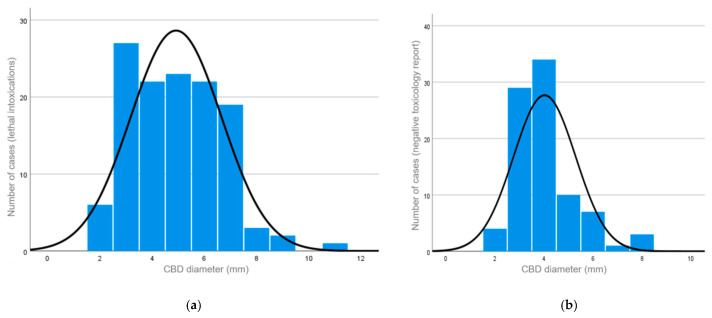

The distribution of CBD diameters in both groups is shown in Figure 2. The diameter ranged between 2 and 11 mm (median diameter: 5 mm) in the study group (Figure 2a) and between 2 and 8 mm (median diameter: 4 mm) in the control group (Figure 2b). In the control group, the diameter of the CBD ranged in males between 2 and 8 mm (median diameter: 4 mm) and in females between 2 and 7 mm (median diameter: 3 mm).

A diameter of >8 mm was considered pathological, similar to the known clinical reference values [ref. 10].

The Mann–Whitney U test showed a statistically significant difference between the CBD diameters in the intoxication group overall, when compared to the CBD diameters in the control group (p < 0.001; r = 0.23).